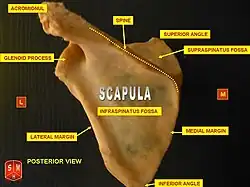

The supraspinous fossa (supraspinatus fossa, supraspinatous fossa) of the posterior aspect of the scapula (the shoulder blade) is smaller than the infraspinous fossa, concave, smooth, and broader at its vertebral than at its humeral end. Its medial two-thirds give origin to the Supraspinatus.

The supraspinous fossa is bounded by the spine of scapula on the inferior side, acromion process on the lateral side and the superior angle of scapula on the superior side.

The human scapula